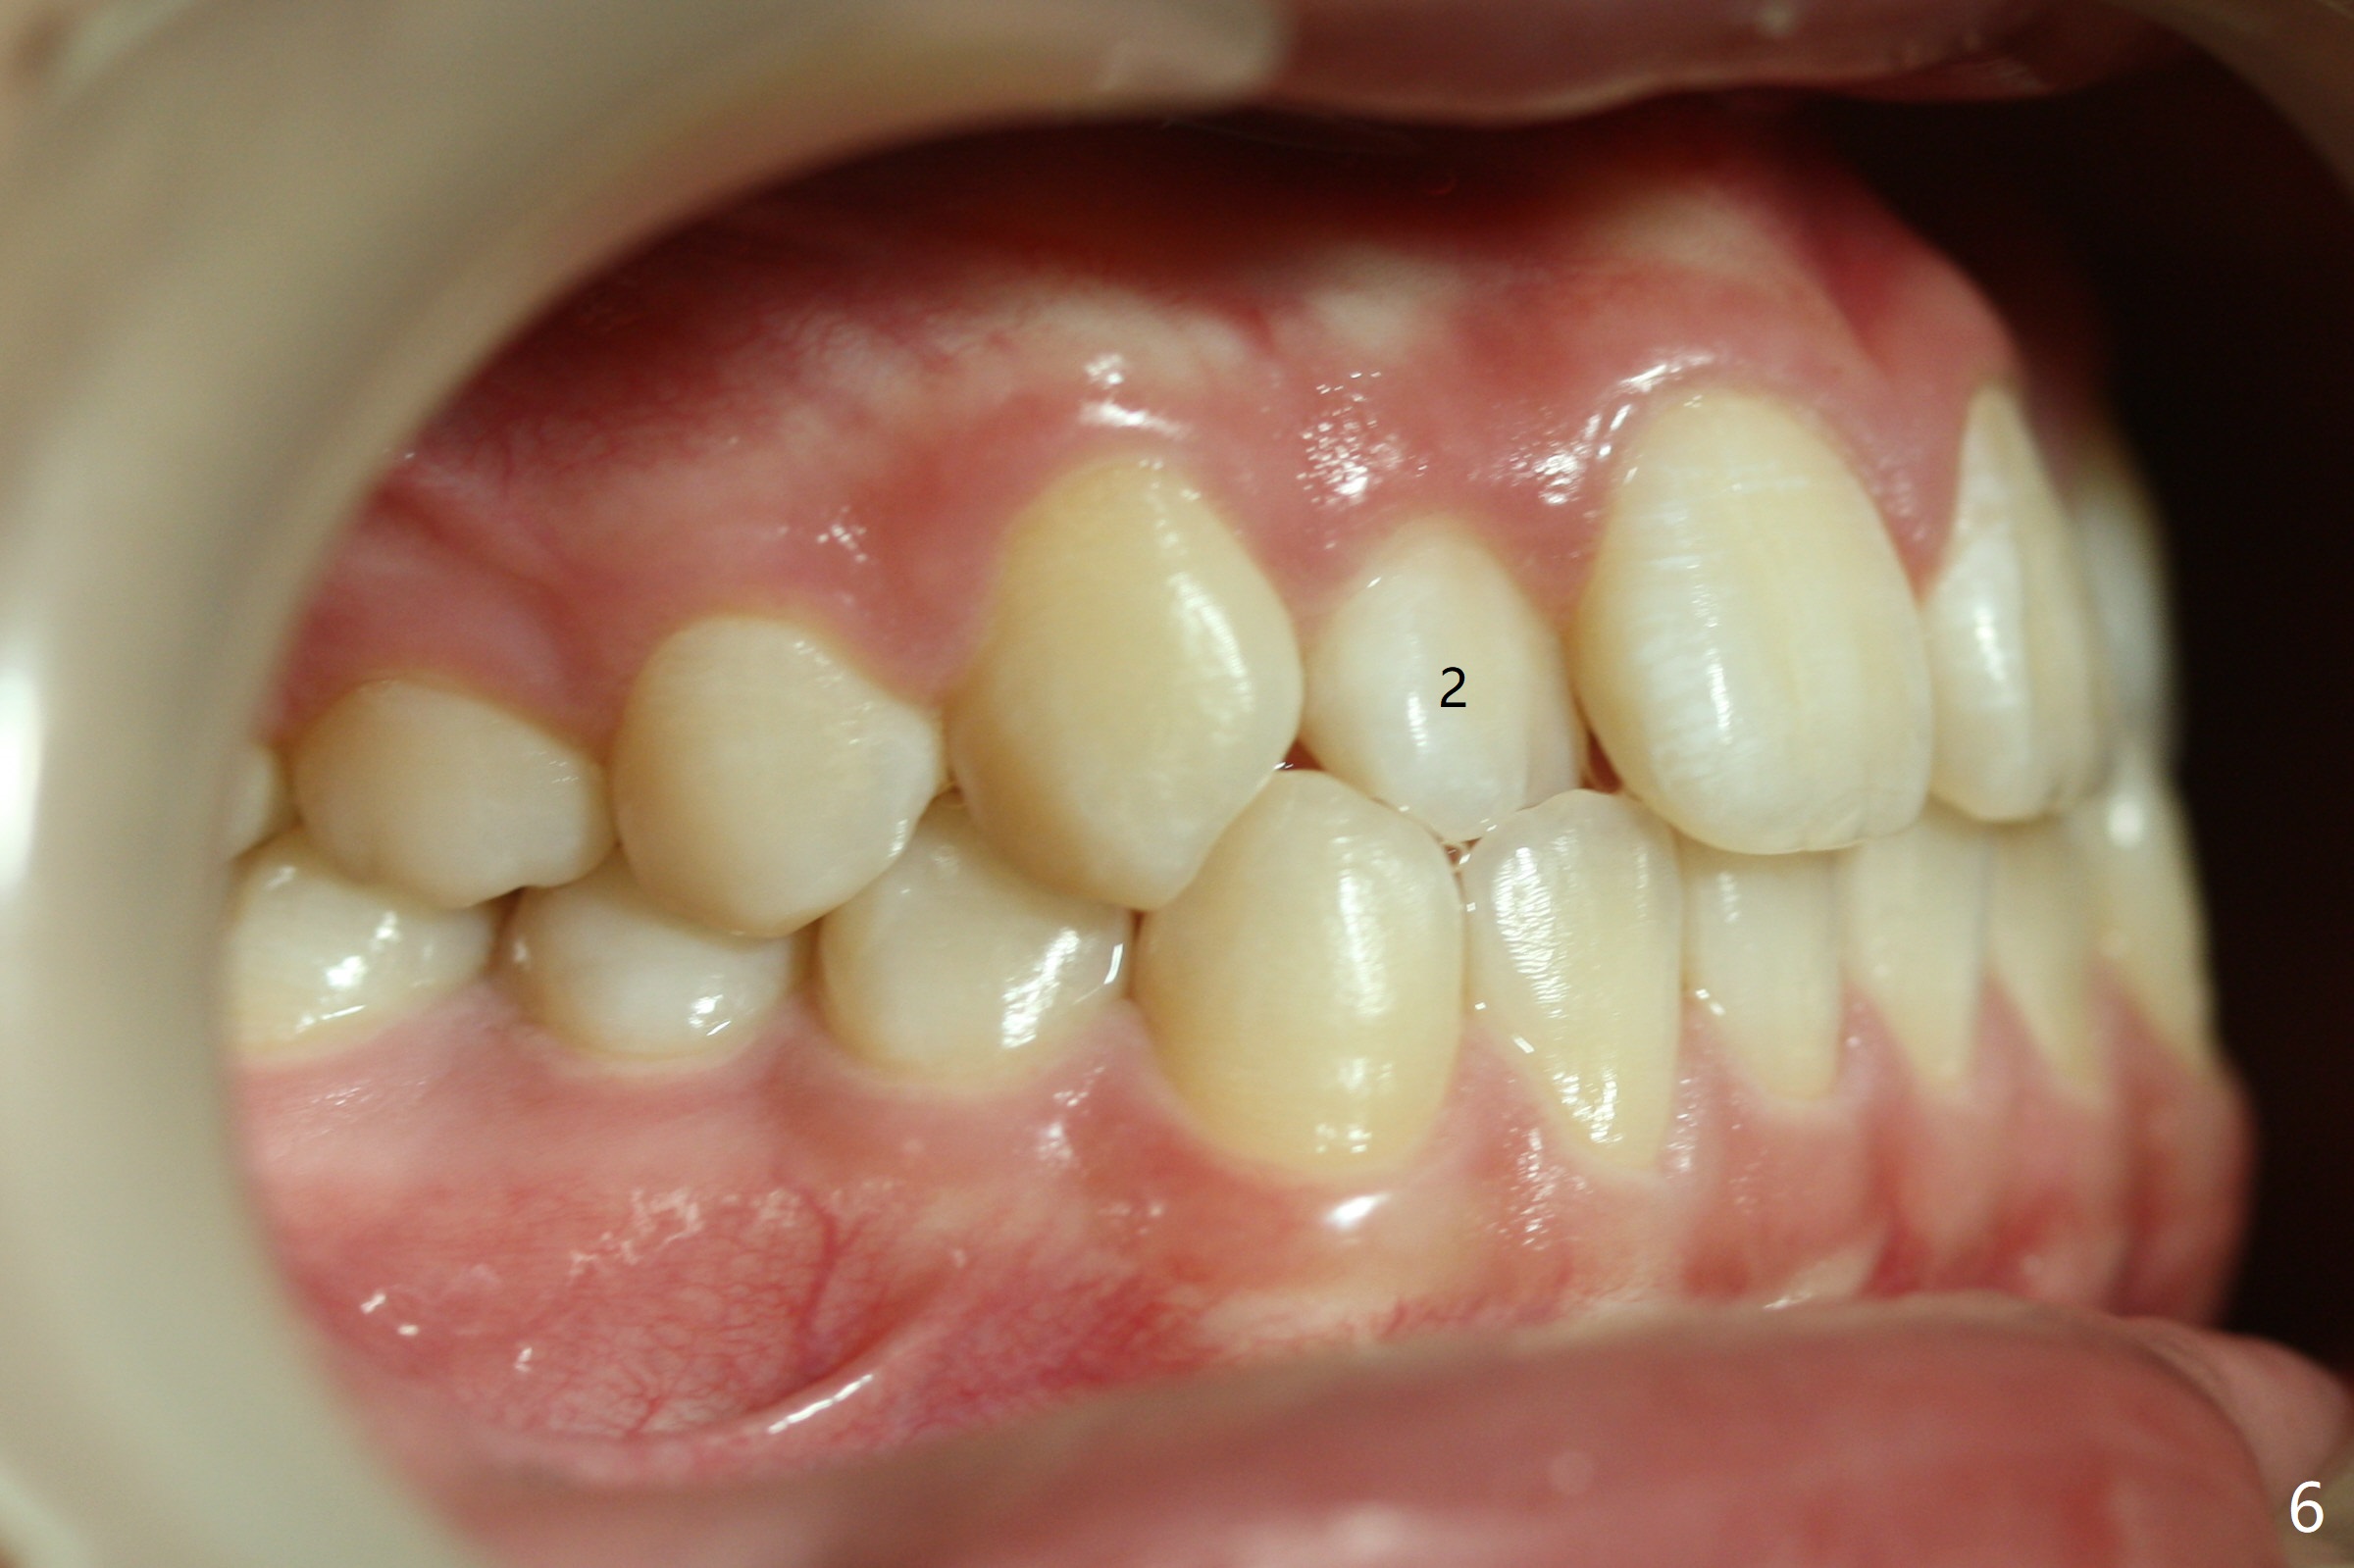

The upper dental midline of a 14-year-old man deviates the left (Fig.1,2,8) with midfacial concavity (Fig.3,4). The upper lateral incisors have cross bite, more severe on the left (Fig.6-8). Can we use open coil spring on the left first, a few months before the right, more or less to help correct the upper midline deviation? Cephalometric analysis shows Class III skeletal relationship (Fig.5,5',11).